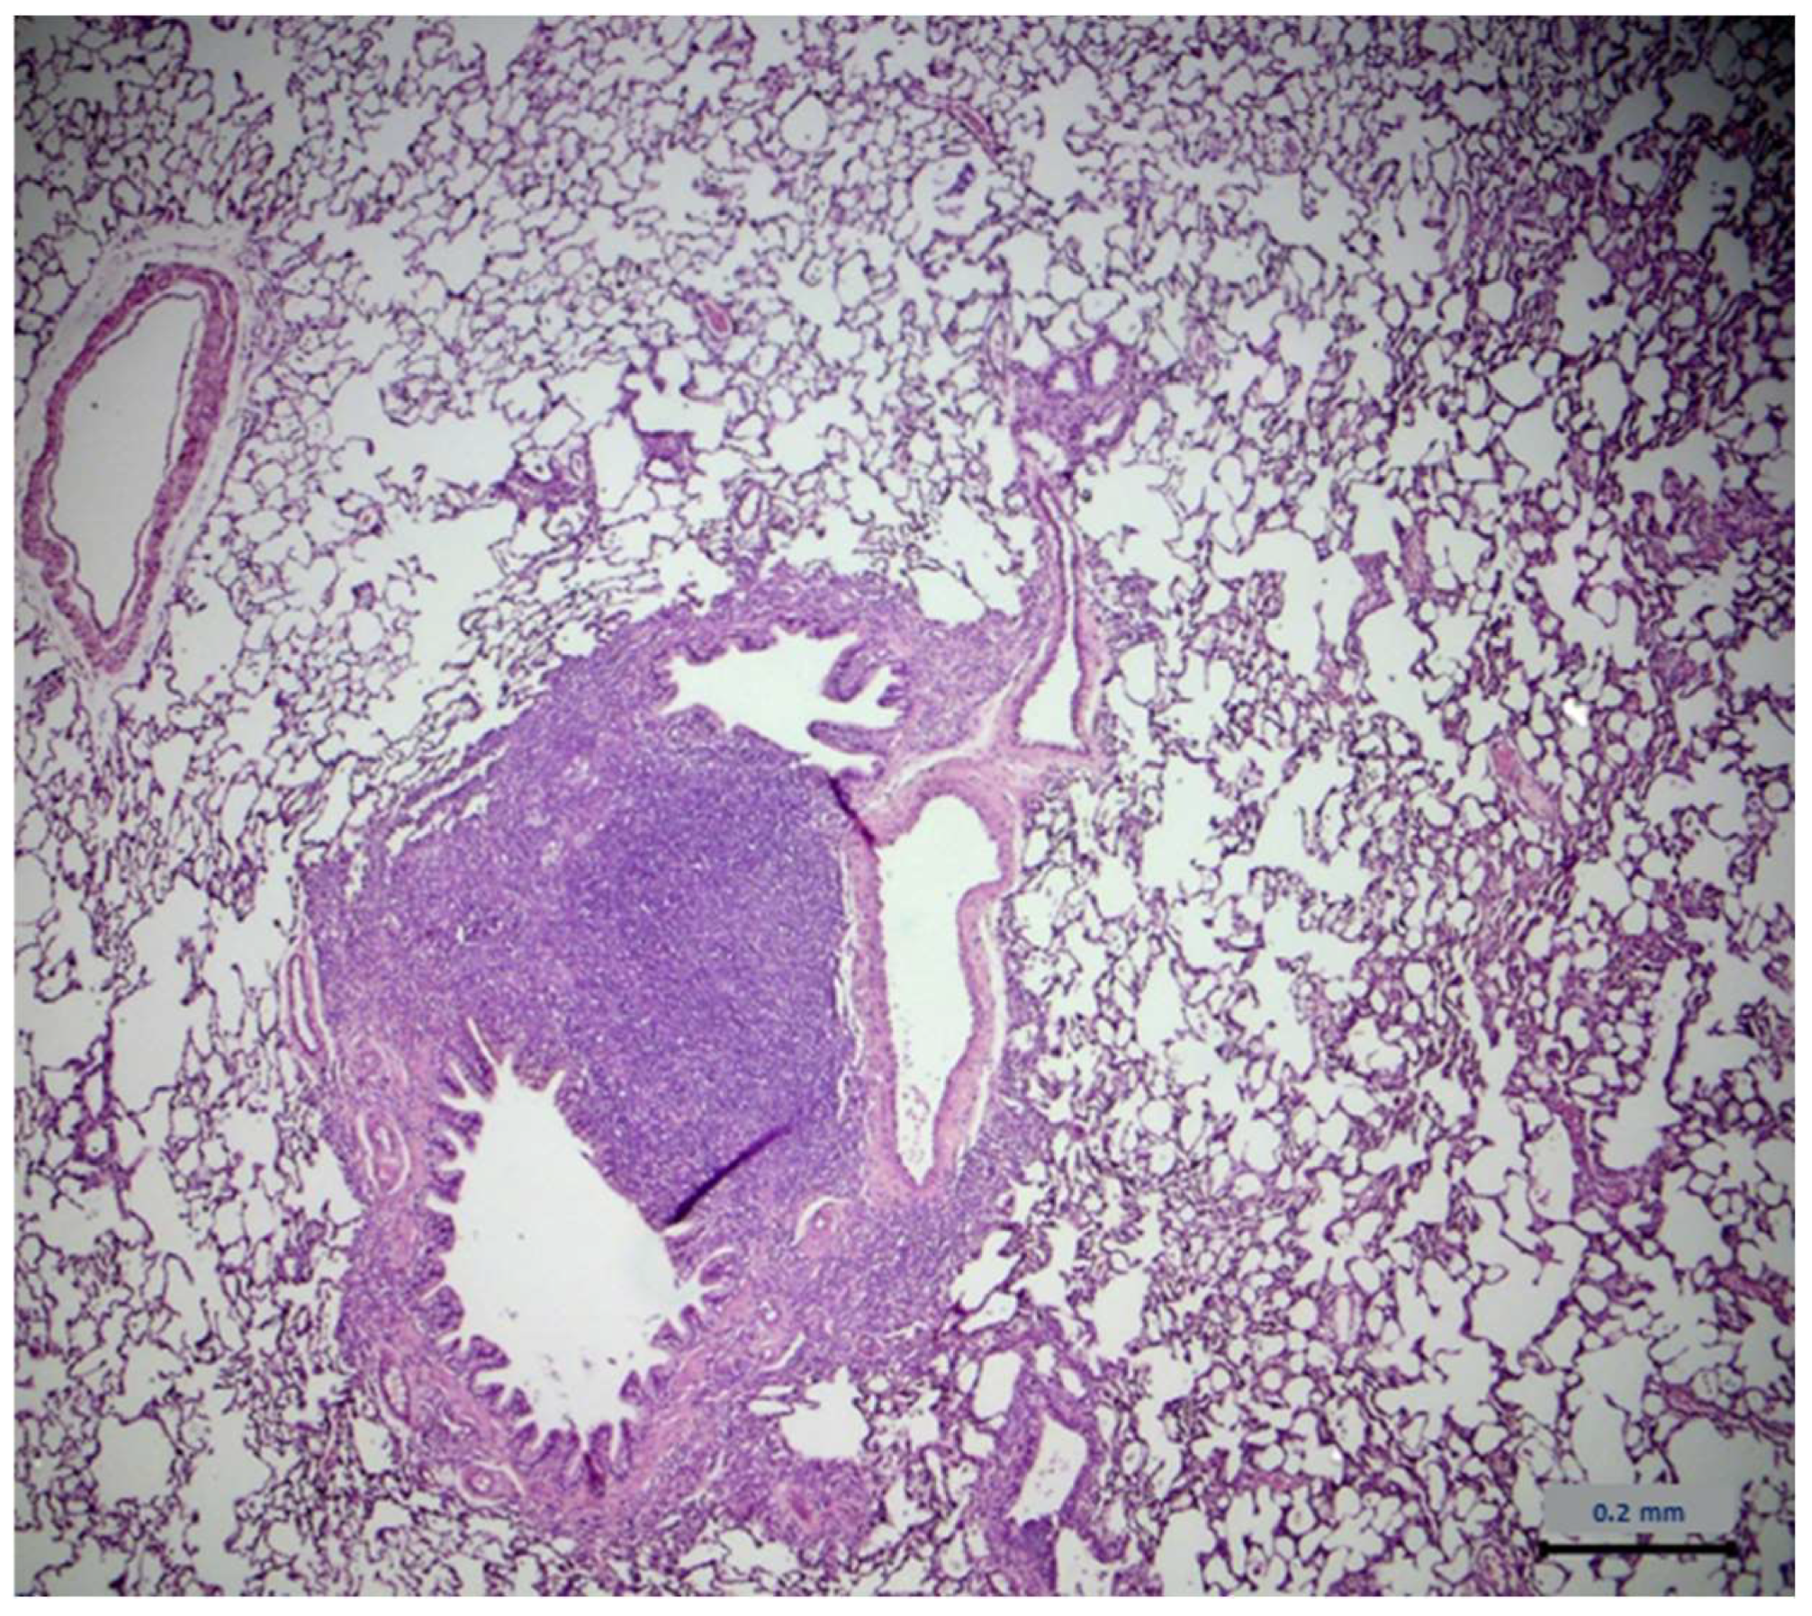

2.7. Histopathological Assessment

- Albers, T.M.; Simon, M.A.; Clifford, C.B. Histopathology of Naturally Transmitted “Rat Respiratory Virus”: Progression of Lesions and Proposed Diagnostic Criteria. Vet. Pathol. 2009, 46, 992–999. [Google Scholar] [CrossRef]

- Slaoui, M.; Dreef, H.C.; Van Esch, E. Inflammatory Lesions in the Lungs of Wistar Rats. Toxicol. Pathol. 1998, 26, 712–713, discussion 714. [Google Scholar] [CrossRef] [PubMed]

- Elwell, M.R.; Mahler, J.F.; Rao, G. “Have You Seen This?” Inflammatory Lesions in the Lungs of Rats. Toxicol. Pathol. 1997, 25, 529–531. [Google Scholar] [CrossRef]

| Lung Type of Lesions | Control Group n = 6 | Extract Group n = 6 |

|---|---|---|

| Architecture | - 1 | - |

| Cell degeneration/necrosis | - | - |

| Inflammatory filtration | 4 2 | 4 |

| Hemodynamic damage | - | - |

| Cell growth disorders | - | - |

| Lung Severity | Control Group n = 4 | Extract Group n = 4 |

| Minimum | - | - |

| Mild | 3 1 | 2 |

| Medium | 1 2 | 2 |

| Serious | - | - |